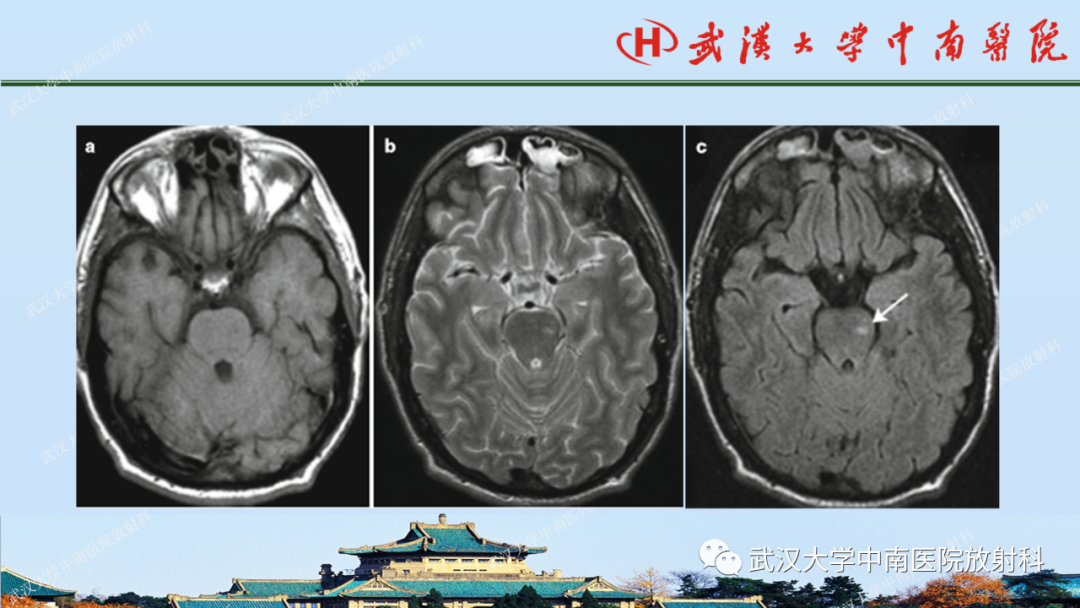

【PPT】脑外伤影像学诊断